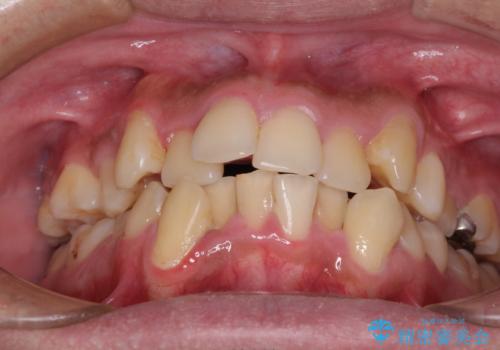

- 八重歯を気にして来院された患者様です。

上下左右の犬歯が八重歯になっており、口元にもやや突出感があるため、上下左右の小臼歯4本を抜歯し、ワイヤー装置にて矯正治療を行うこととしました。